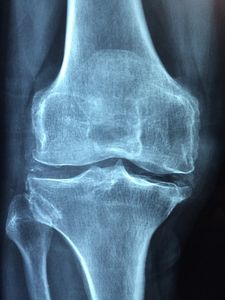

Röntgenbild: Knie oft von Arthrose betroffen (Foto: pixabay.com, Taokinesis) |